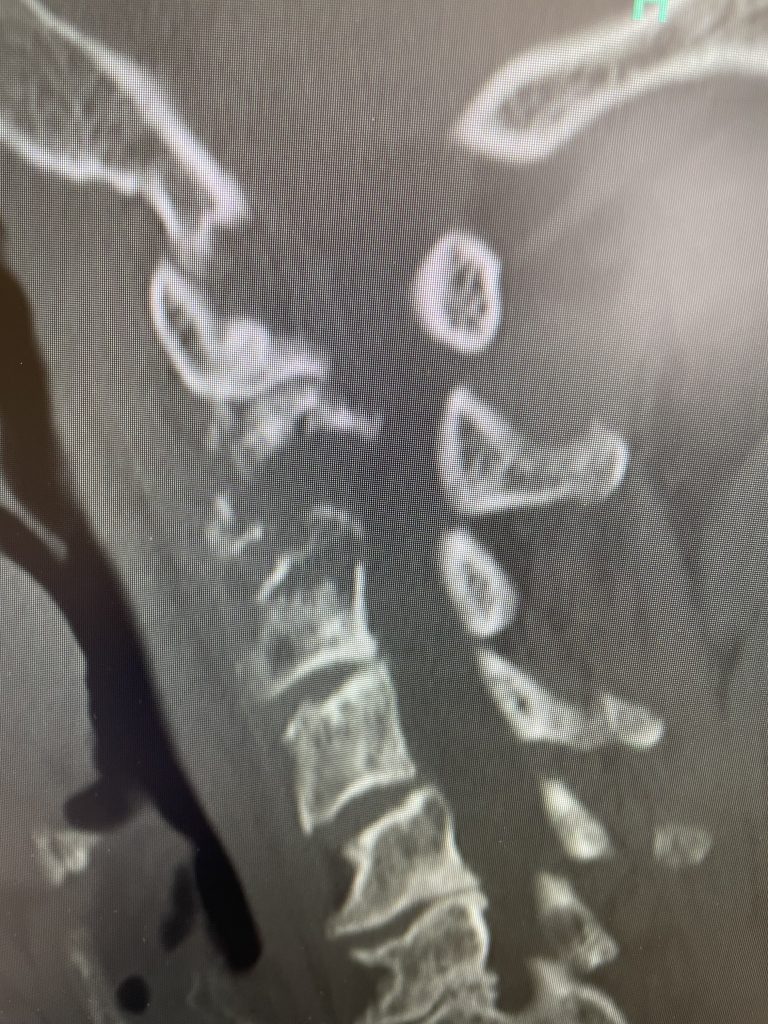

Fig 2: Sagittal CT scan demonstrating progression of disease into C3 vertebral body

After several months he represented with worsening neck pain and placed in a hard collar. He had a repeat CT scan which showed some progression of disease now more affecting the C3 vertebral body (Fig 11). The patient had flexion extension x-rays which showed stability. The patient was referred to pain management for better control. He was placed in a hard collar. Given the progression of disease after radiation, three columns of the spine affected, progression of neck pain, potential for collapse of the bone and retropulsion into the canal causing quadriplegia, surgical stabilization was offered to the patient. Given the poor bone quality, as one can assume that the multiple myeloma could extend to other adjacent bones, it is challenging to stabilize the patient with good fixation. Options would include stabilizing with hardware and fusion from C1 to C5 which would provide stabilization above and below the area of potential collapse. Another option would be to go from occiput to C5. This is a more morbid procedure and really severely limits head movement. Your “yes” and “no” movements are between your occiput and C2. Most people do not realize that sixty percent of your head and neck motion is between the occiput and C2. The rest is distributed amongst the other cervical vertebrae. If a fusion was carried up to C1, then the patient would not lose as much motion not to mention the significantly increased exposure and risk with an occipital-cervical fusion. The patient declined surgical treatment at this point knowing all the risks. He agreed to wear his collar. He was in better pain control. He will be followed closely.